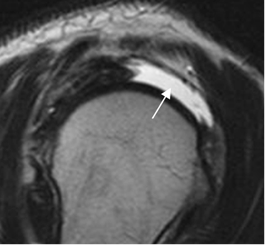

Fig 126. Atrofia del supraespinoso.

RM sagital en T2. Ruptura de evolución crónica, con atrofia del supraespinoso. El músculo se sitúa por debajo de la línea tangente.